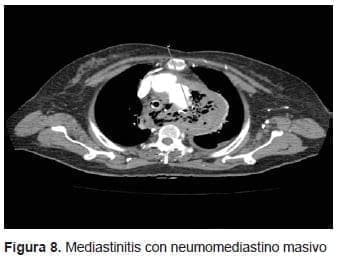

Ingresó taquicárdica e hipotensa con baja perfusión distal:

Se diagnosticó choque hipovolémico y se inició reanimación hídrica con hemoderivados; además, requirió asistencia respiratoria y hemodinámica. En la endoscopia de vías digestivas se observó un gran coágulo en el esófago que, al retirarse, dejó ver un defecto en la pared esofágica a 25 cm de la arcada dental, sugiriendo la presencia de una fístula. Se practicó una angiotomografía de tórax en la que se encontró la endoprótesis en buena posición, aunque había signos de mediastinitis y de neumomediastino masivo (figura 8).